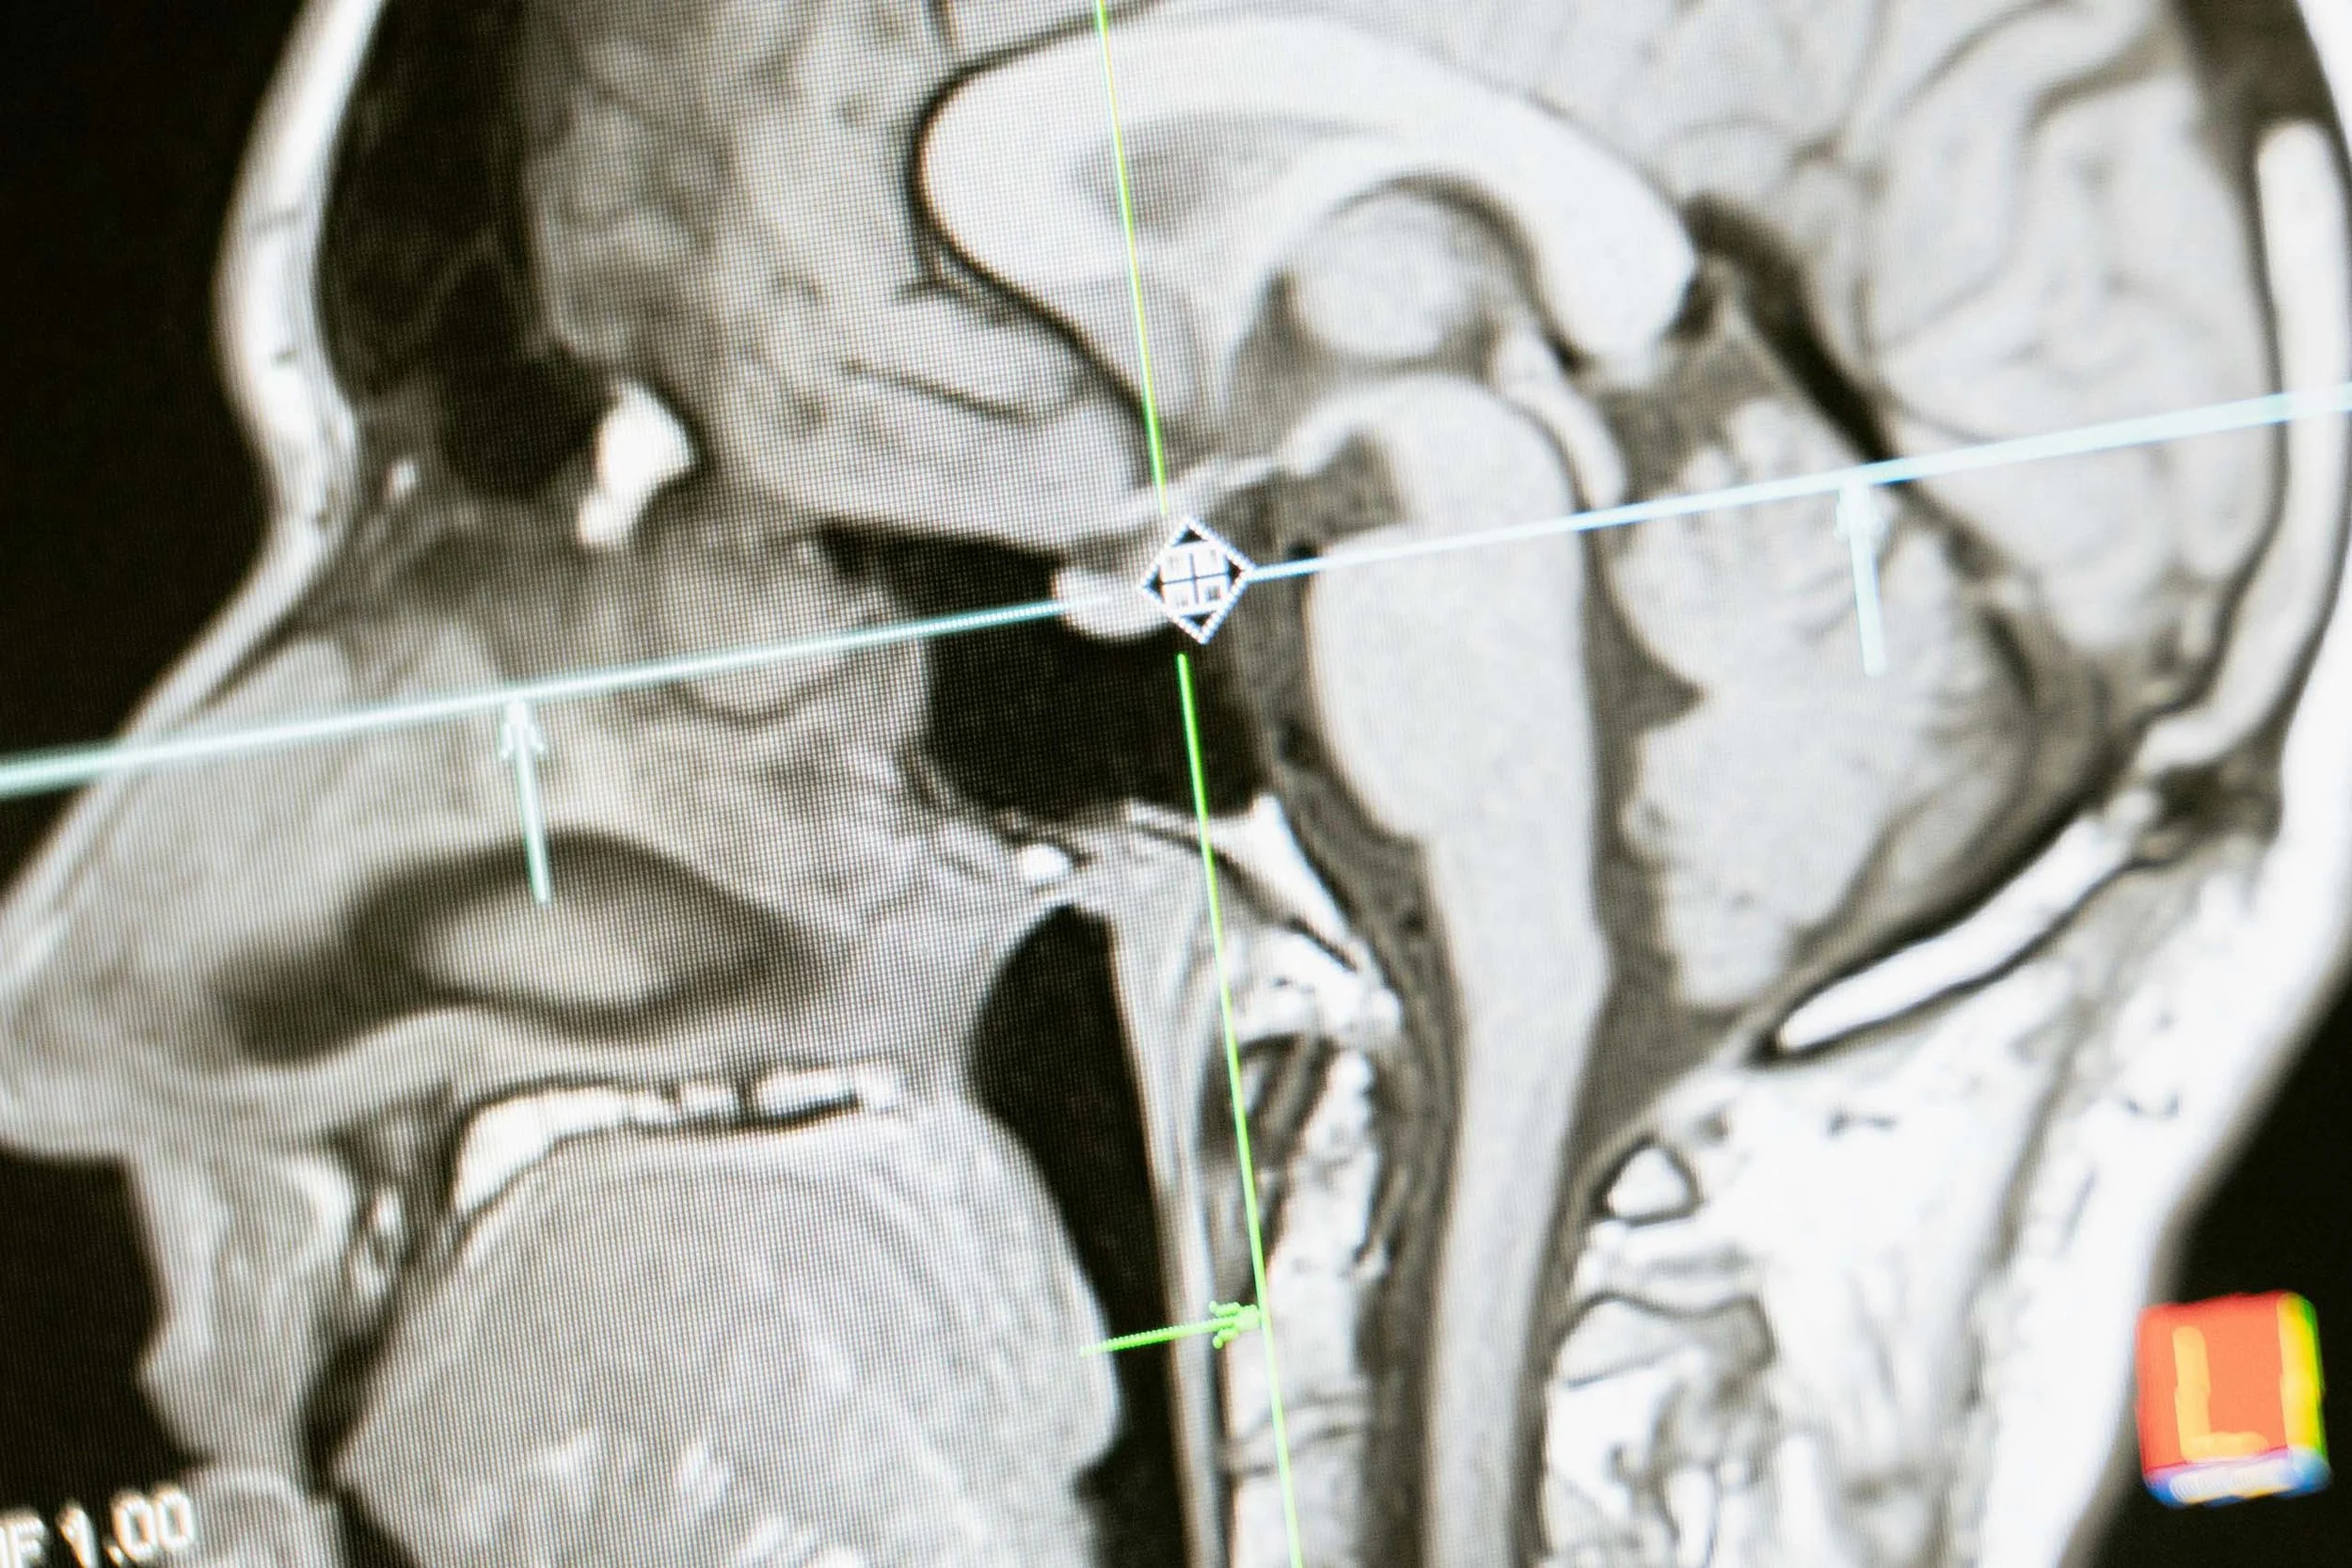

Sagittal MRI scan of the human brain and brainstem with targeting lines overlaid, illustrating neuroimaging analysis.